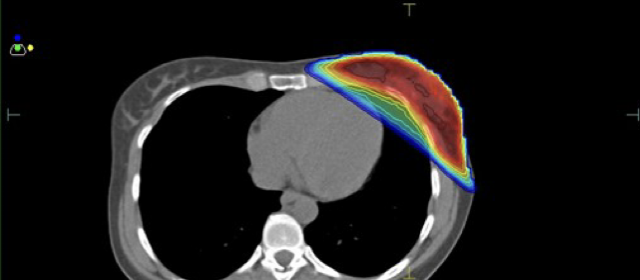

Κατανομή δόσης με την τεχνική ABC

Ελαχιστοποίηση δόσης στην καρδιά και τον πνεύμονα